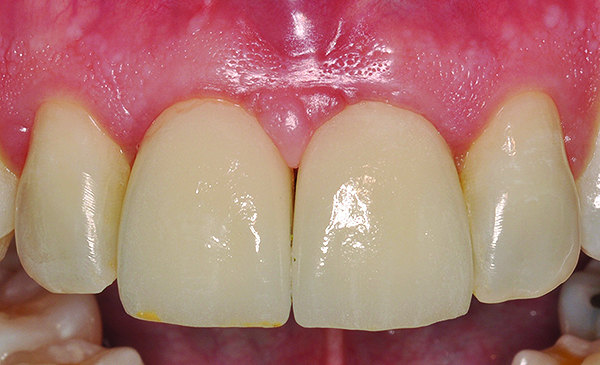

The DICOM (digital imaging and communications in medicine) images are then imported from the CBCT files into one of many commercially available implant-planning software programs. The surgeon and restorative dentist can then collaborate in choosing the precise position, angulation, and depth of implant placement, as well as the implant type, based upon a desired prosthetic outcome. Rosenfeld et al coined the term “collaborative accountability” to describe the pretreatment analysis and subsequent negotiated compromises between surgical and restorative colleagues on implant positioning and restorative design based upon anatomic limitations and the team’s willingness and ability to overcome them.3 Additionally, this pretreatment evaluation is invaluable in creating realistic patient expectations. Figure 1 through Figure 6 demonstrate a case showing 3-dimensional (3-D) presurgical planning, radiographic evidence of the plan’s execution, and 2-year follow-up. As a result of 3-D planning and subsequent guided implant surgery, the patient wound up with a pleasing, nature-like esthetic outcome (Figure 5).

Fig 5. Clinical presentation of implant Nos. 8 and 9, 2 years after implant placement.

Figure 5